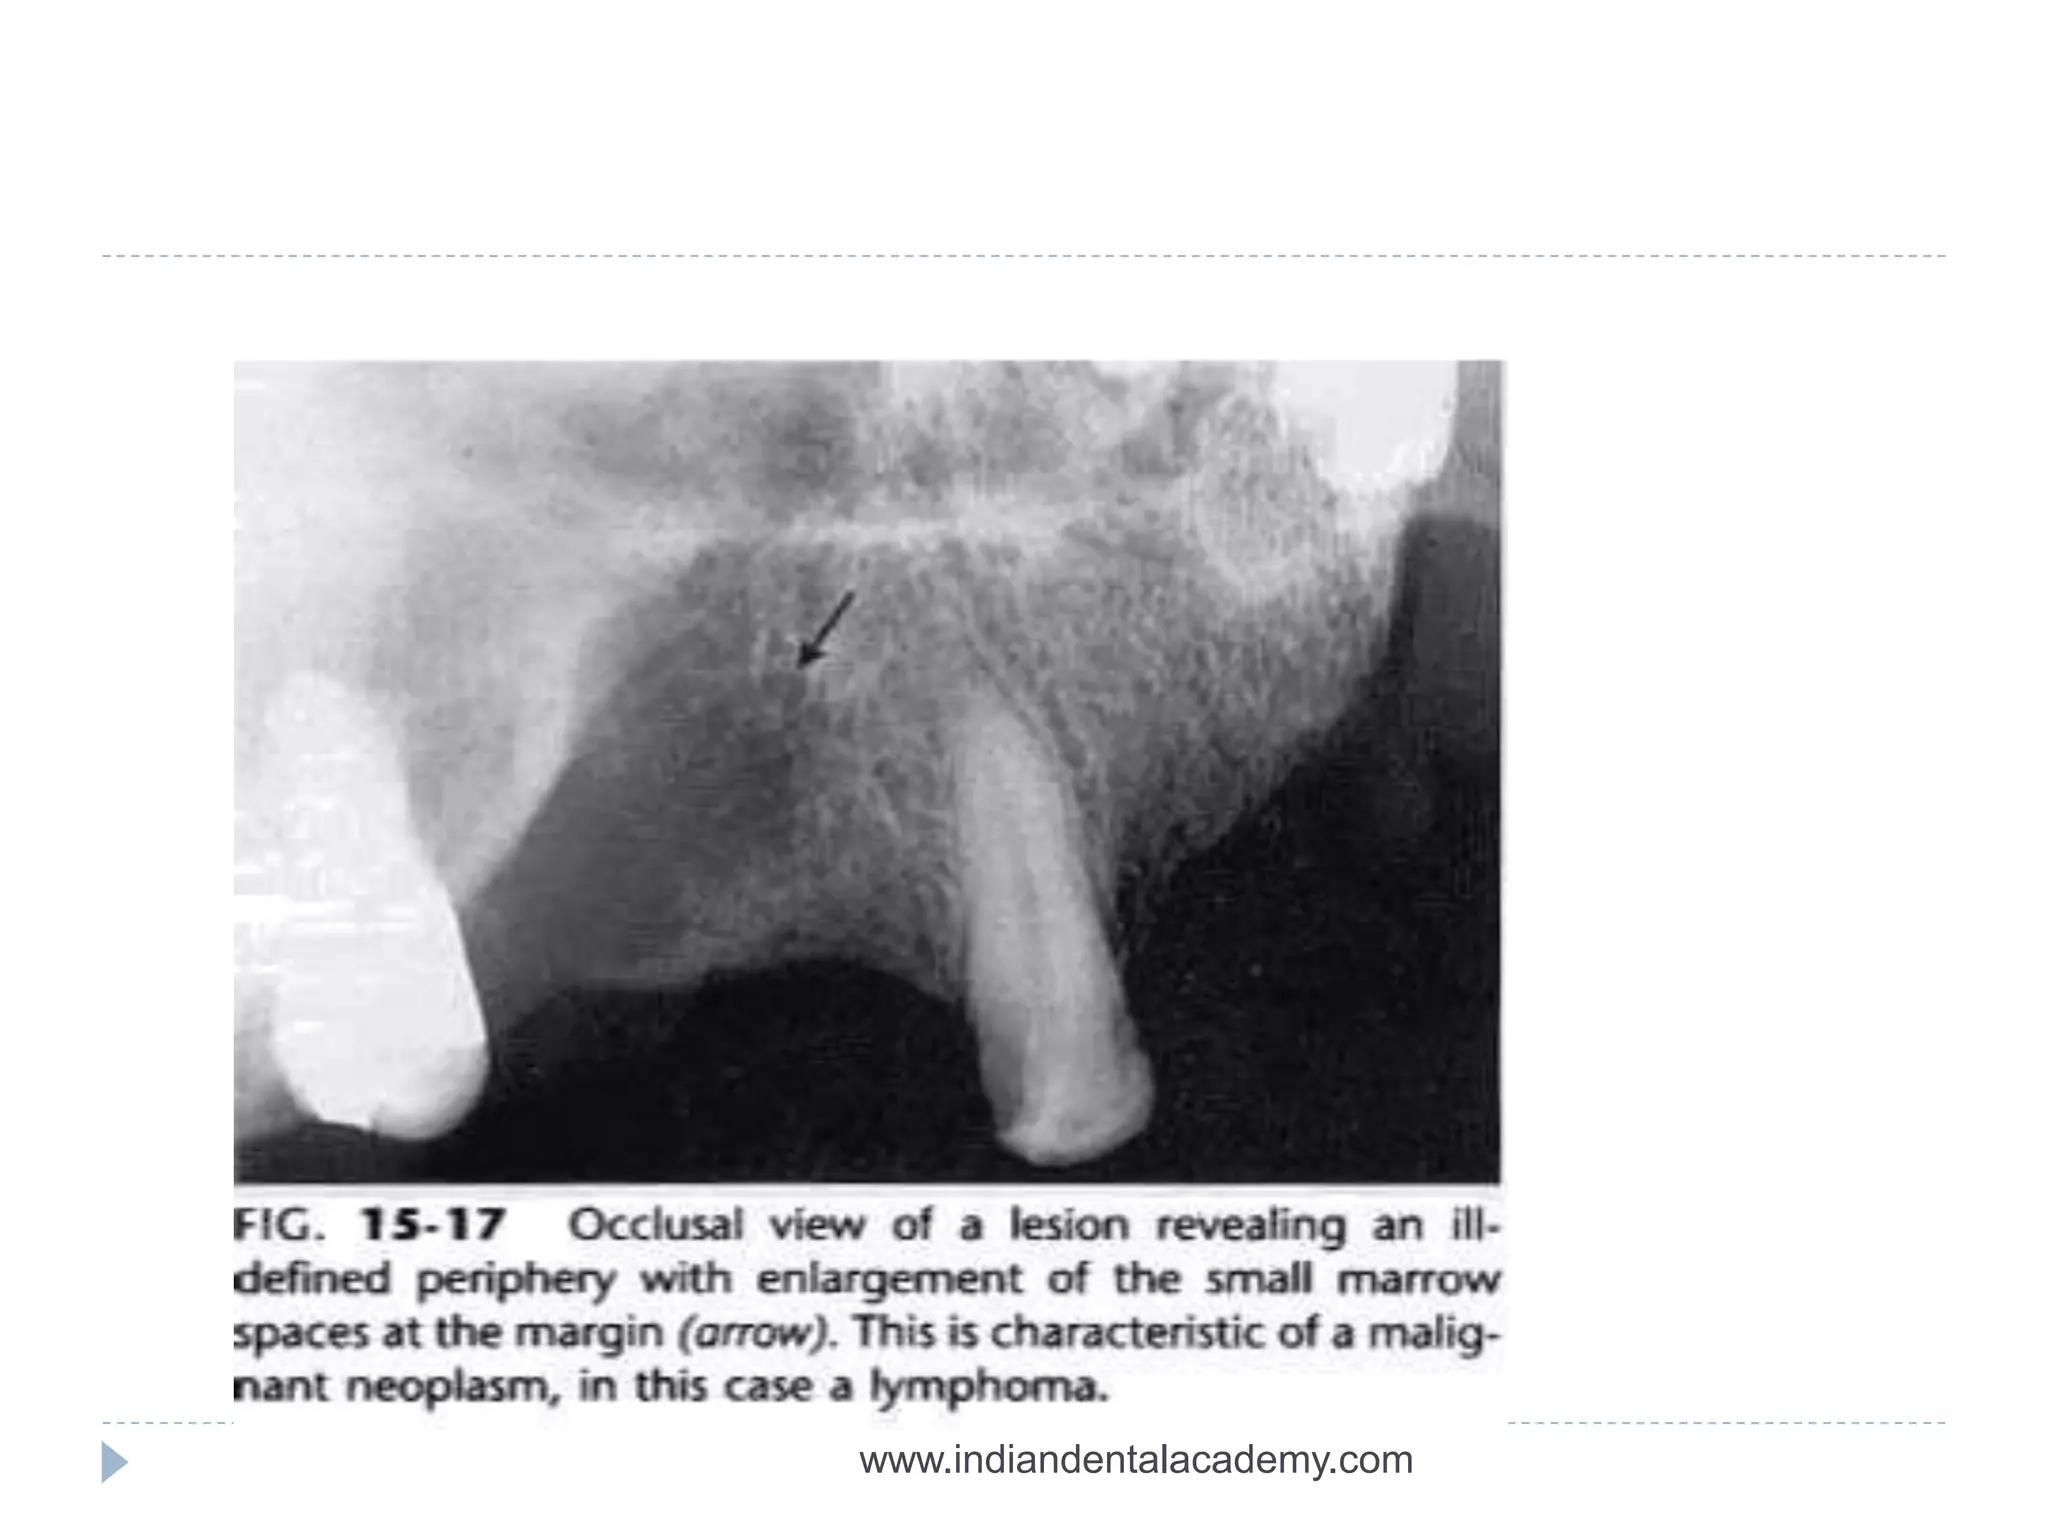

ILL DEFINED BORDERS

 Invasive border-bone destruction-malignancy